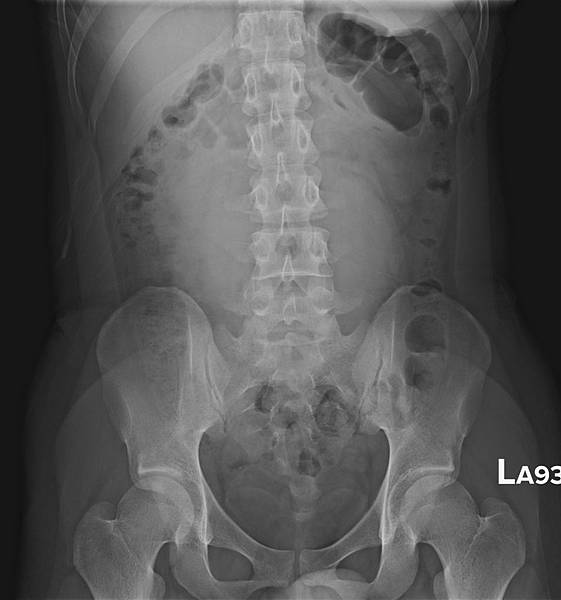

KUB看不出她的病有多嚴重:

72歲女性,乙狀結腸(黃箭頭)充滿糞便,但她會告訴你,她每天都有解便。如上圖所示,這樣的病例,病人直腸(藍箭頭)糞便清得很乾淨。